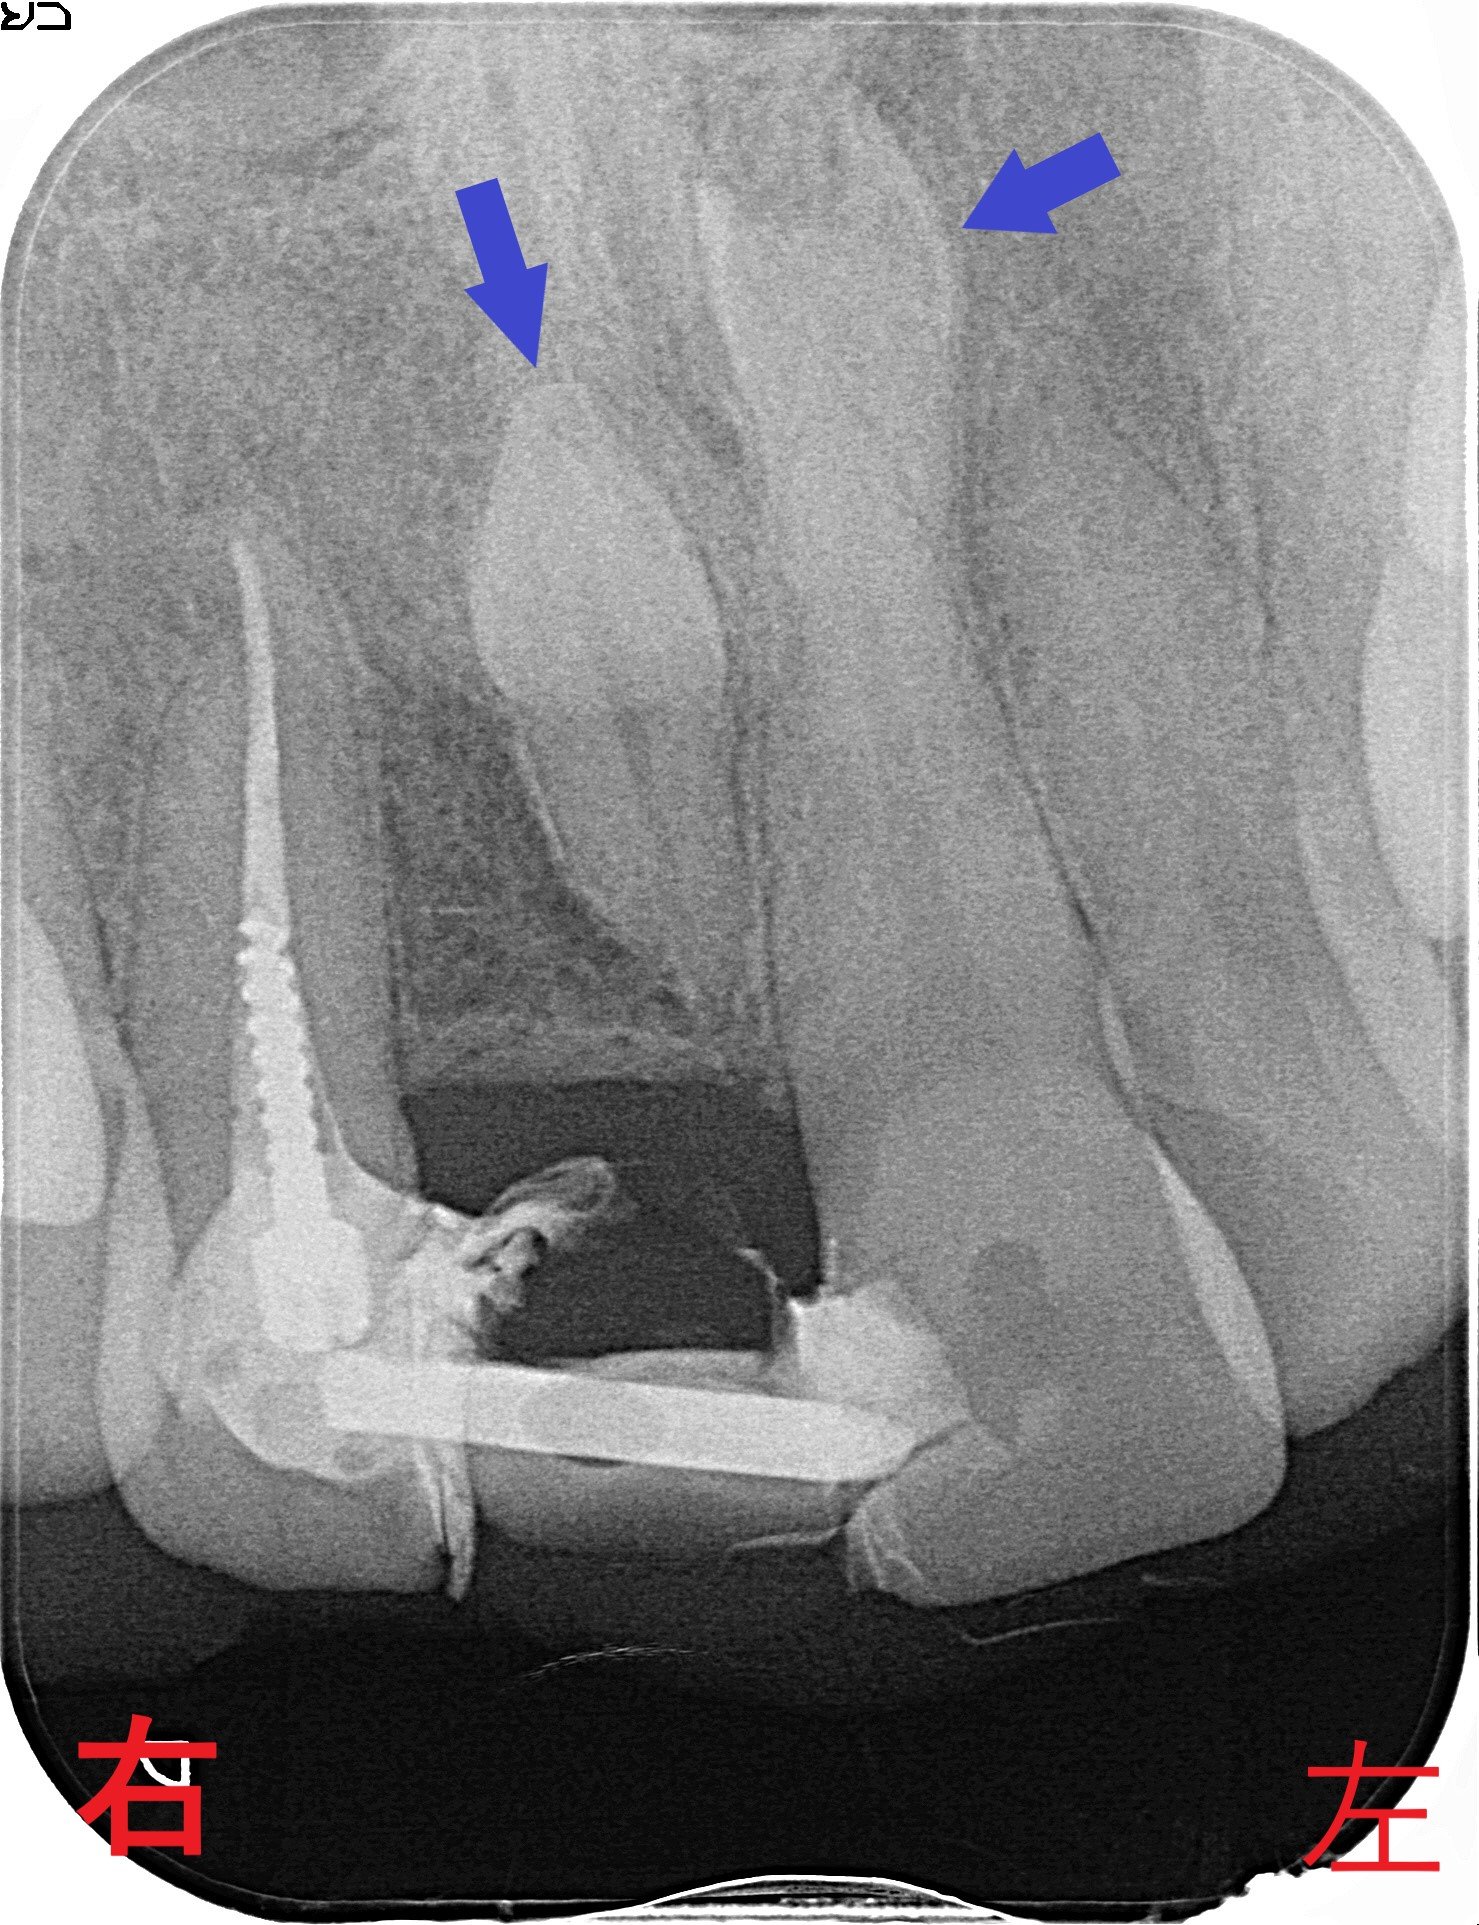

【レントゲンによる診断】

右上前歯は仮歯であり、以前通院されていた歯科医院にて抜歯され、両隣の歯と連結された状態でした。

レントゲン写真からは、仮歯の下に2本の過剰歯(青色矢印)が確認されました。